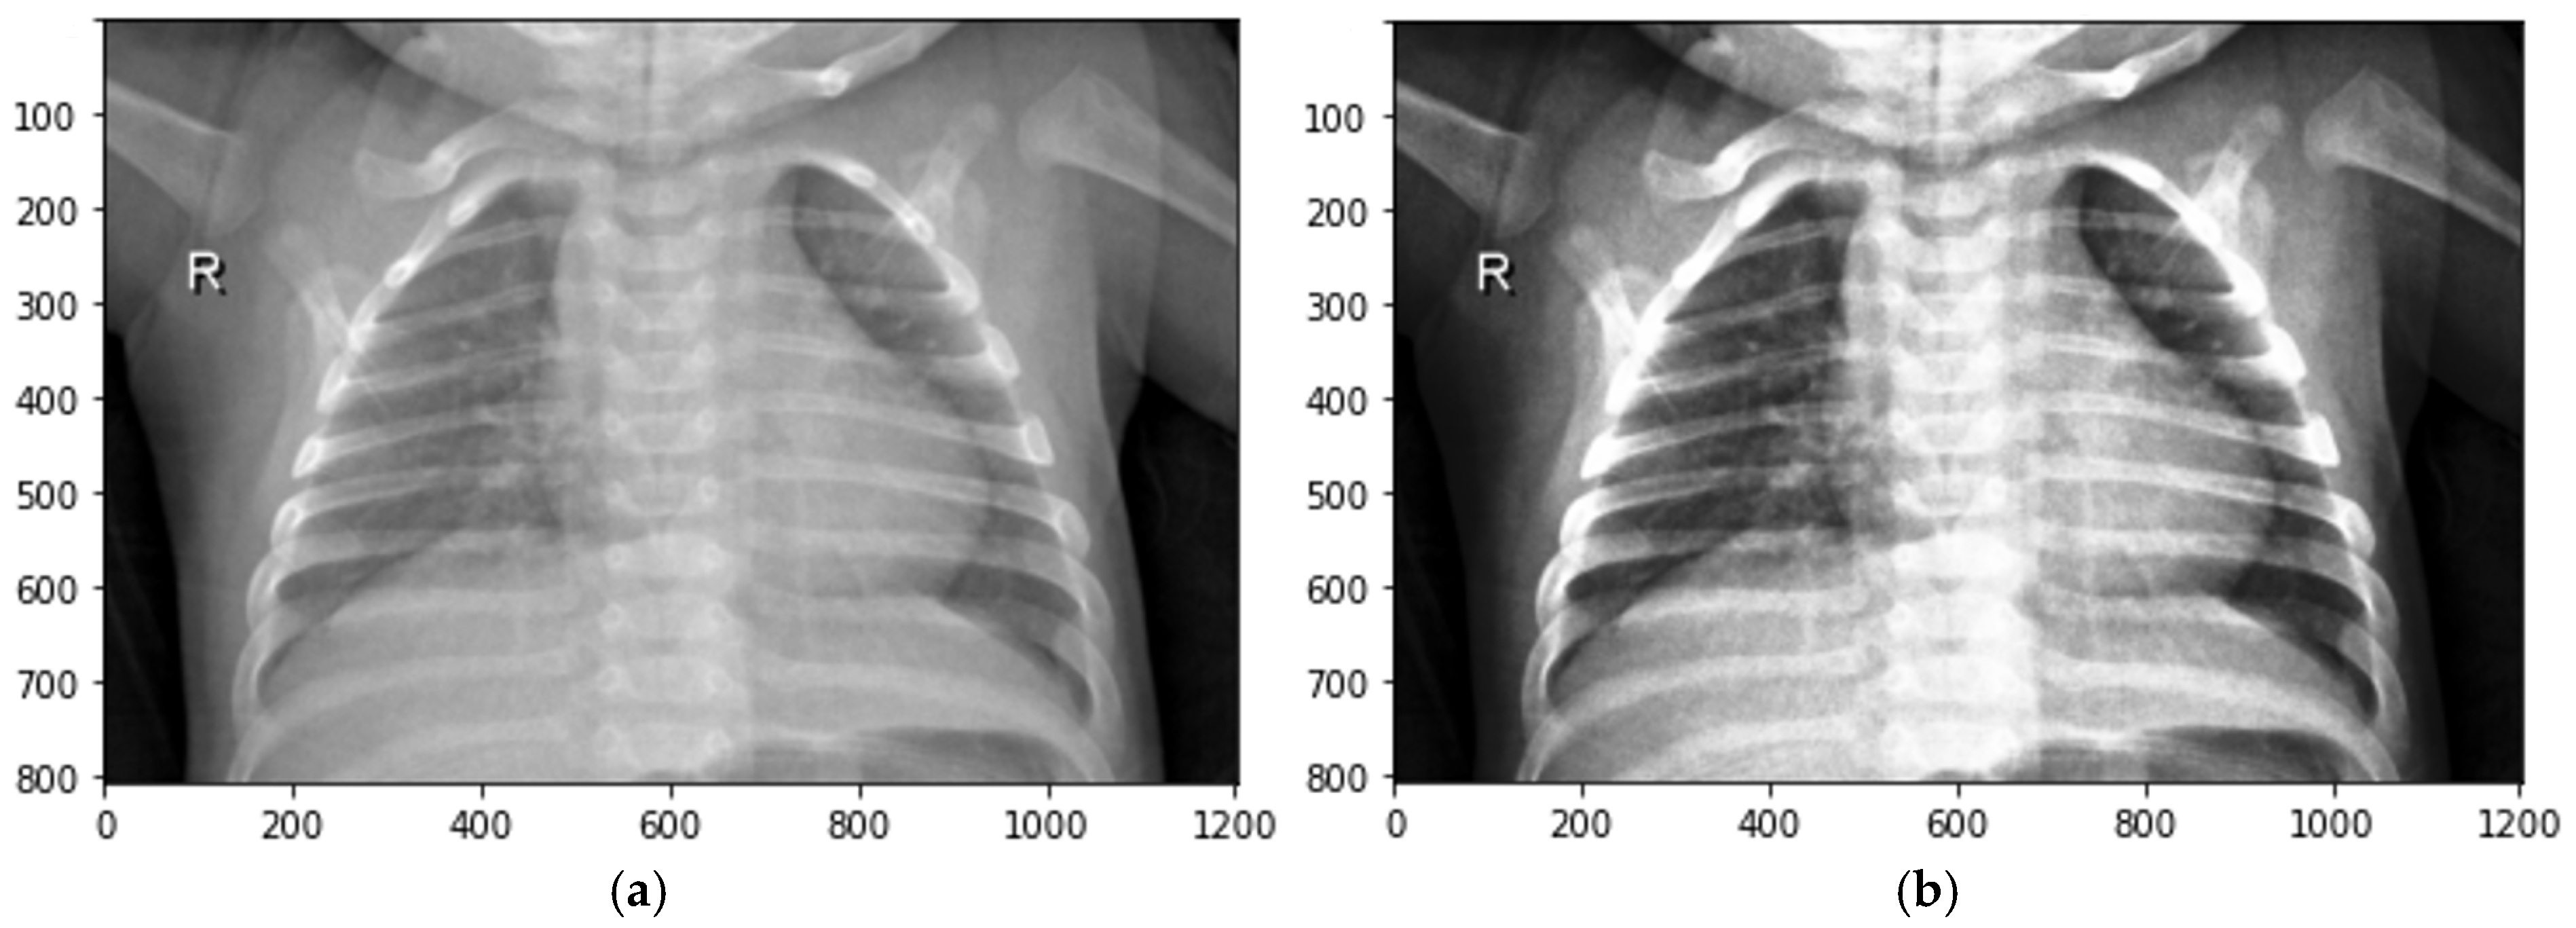

where s > 0. See Figure 4.

Figure 4.

Transformations of local contrasts based on histogram length functions: (a) original image; (b) histogram of original image; (c) defuzzified image; (d) histogram of defuzzified image.